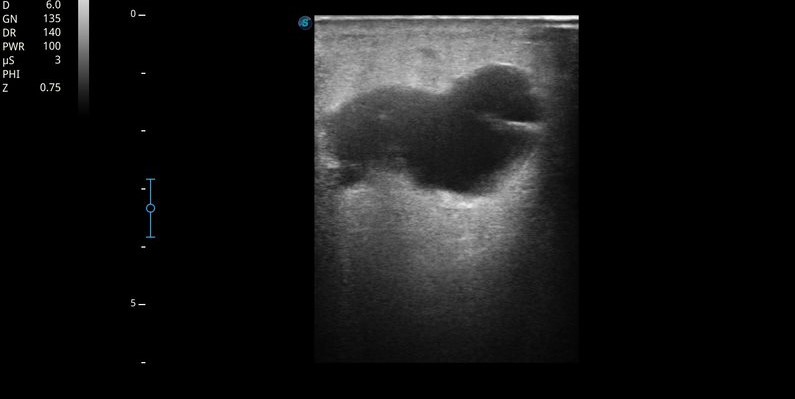

Ecografía MII: Sistema venoso profundo permeable, compresible en todo su recorrido, sin contenido hiperecogénico en su interior. Sistema venoso superficial permeable. Se objetiva a nivel de tejido celular subcutáneo de región interna de tercio superior de muslo izquierdo, colección anecoica, tabicada, no vascularizada, con algunos ecos en su interior, de unos 3-4 cm, con sombra acústica posterior. Importante edema en empedrado en pierna izquierda compatible con celulitis.